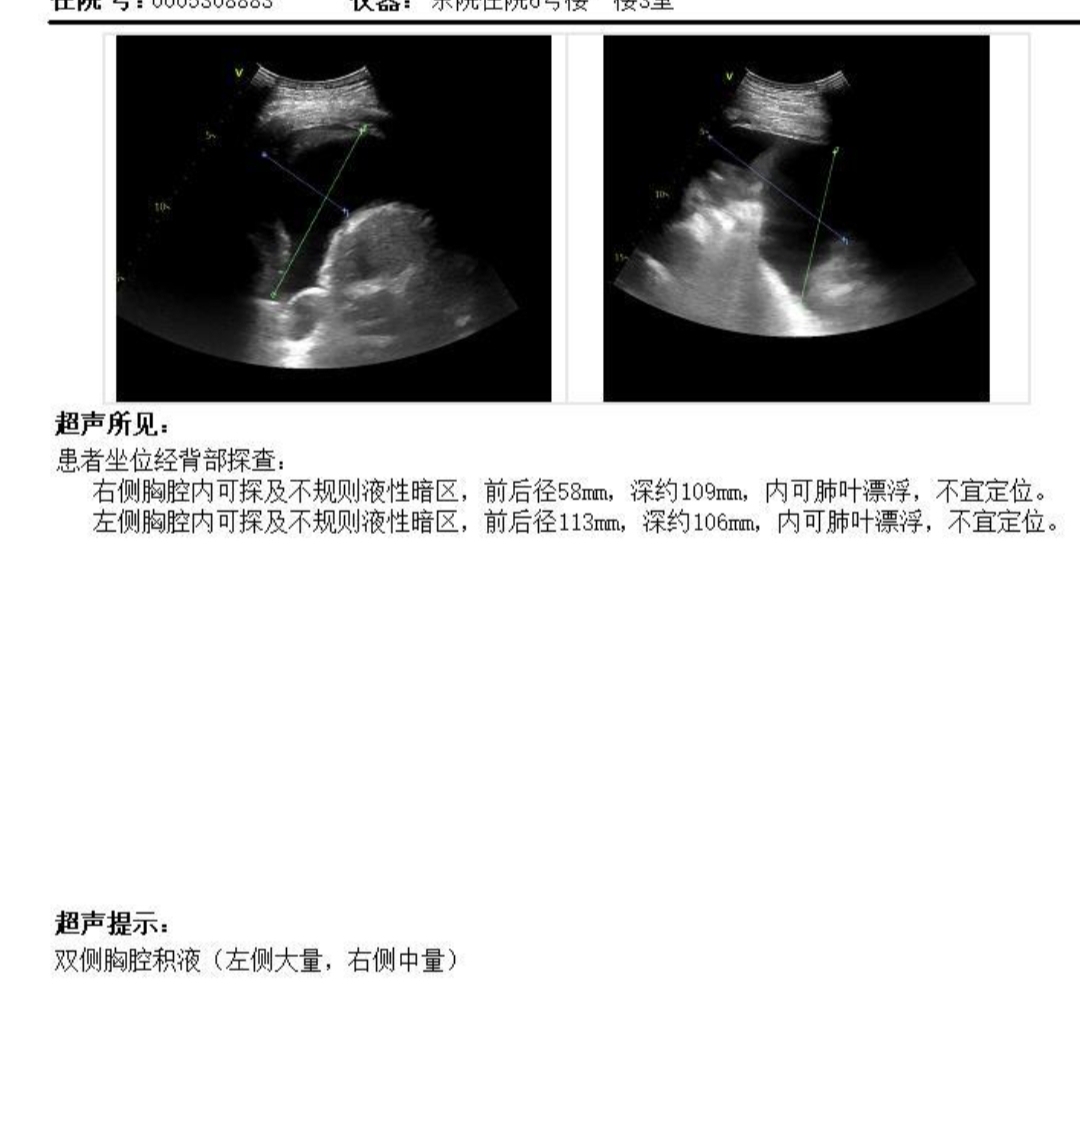

胸腔积液1个月了,现在双腔每天都得至少引流500ml,不然胸闷气喘,医生不敢让多放,现在产生的越来越多了,不知道怎么治疗了。